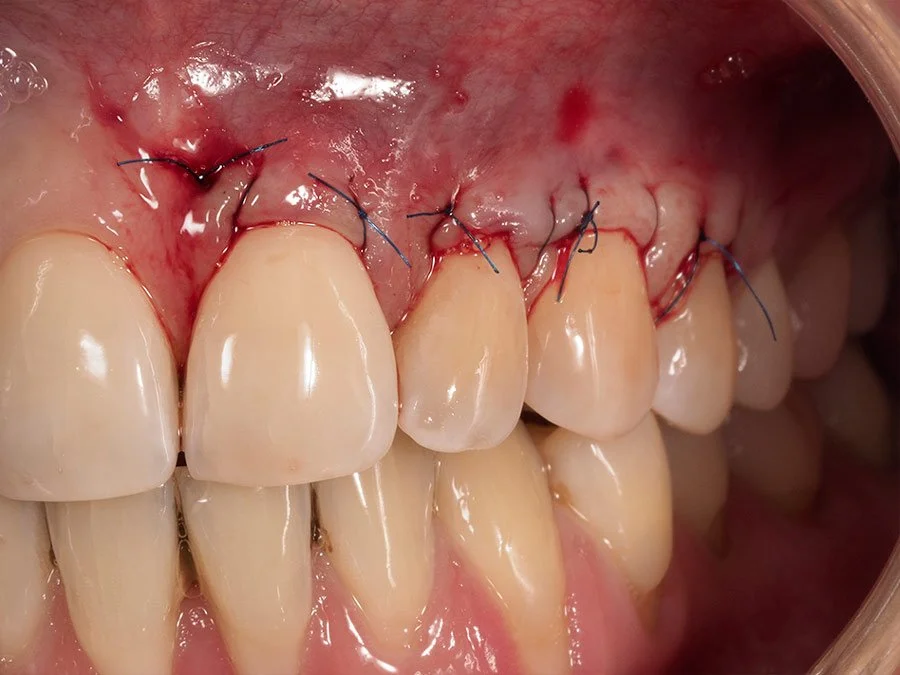

4. Suturas finas para mantener el injerto en su lugar.